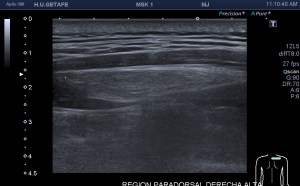

Los vientres anteriores de los músculos Digástricos, que son el objeto del desarrollo de este Post, son dos estructuras musculares redondeadas en el corte transversal, imagen 1, y alargados si los estudiamos en el eje largo, imagen 3, mira:

Ecográficamente los músculos digástricos en eje corto tienen semiología hipoecogénica, en aspecto de noche estrellada, como la de hoy, y en el eje largo en forma de penacho o en forma de plumas con las fibras alargadas y paralelas a la superficie.

Acostúmbrate a mirar esta anatomía en los estudios de cuello sobre todo en pacientes infantiles, por posible localización de adenopatías. En la edad adulta pueden objetivarse cambios de grosor, infrecuentemente, en esta musculatura por diferentes motivos.